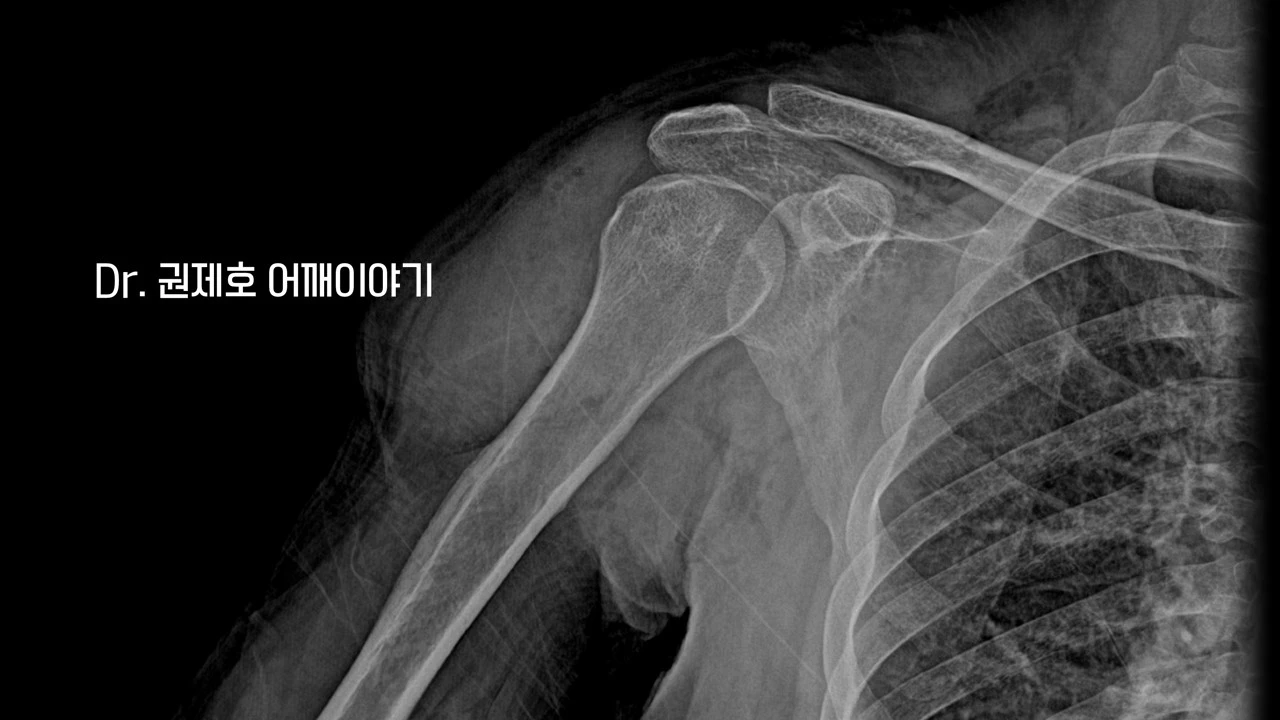

처음에 진료를 보시러 오시면, 기본적인 검사를 하고 진료를 보게 된다. 그 기본적인 검사는 바로 어깨 방사선 촬영이다. 사진에서 보면 '견봉'이라는 뼈 밑으로 오랜 세월에 걸쳐 생긴 '골극'이 관찰된다. 골극이라는 것은 뼈가 자라나는 현상을 나타낸다.

수술 후 엑스레이를 보면 견봉 밑에 자라는 골극이 없어진 것이 확인된다. 인대를 끊어지게 만드는 근본적인 원인 제거는 확인되었다.